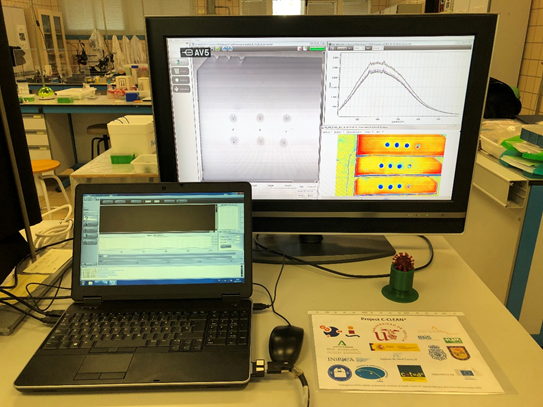

Un equipo de investigadores españoles, coordinado por la Universidad de Sevilla y con participación del Observatorio de Calar Alto y del Instituto de Astrofísica de Andalucía (IAA-CSIC), ha podido detectar el coronavirus causante de la Covid-19 mediante una nueva tecnología óptica. Esta herramienta sería potencialmente utilizable como método de cribado masivo, rápido y fácil de implementar.

Una colaboración multidisciplinar española, cuyos primeros resultados se recogen en la revista Scientific Reports, del grupo Nature, ha obtenido resultados en la detección de SARS-CoV-2 en exudado nasofaríngeo de personas sintomáticas (las mismas muestras usadas en una prueba PCR) con una sensibilidad del 100% y una especificidad del 87,5%. También se ha conseguido detectar la presencia de SARS-CoV-2 en saliva fresca de personas asintomáticas, así como detectar, diferenciar y cuantificar dos tipos de virus sintéticos (lentivirus y coronavirus sintéticos) en dos tipos de biofluidos (solución salina y saliva artificial).